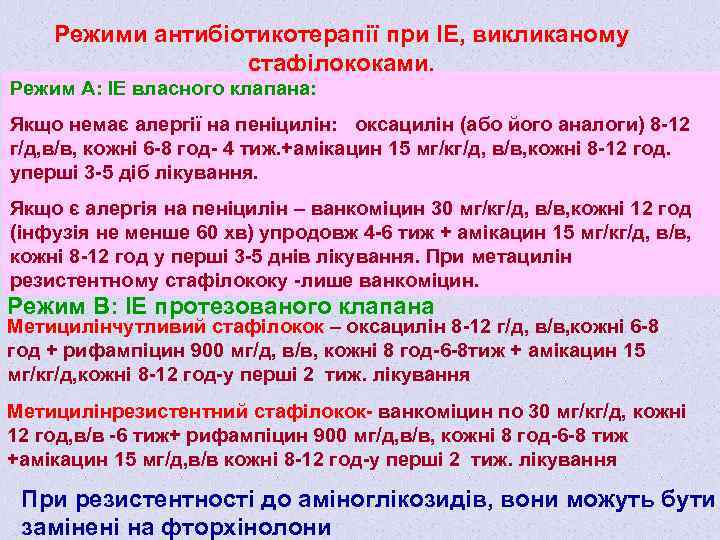

Режими антибіотикотерапії при ІЕ, викликаному стафілококами. Режим А: ІЕ власного клапана: Якщо немає алергії на пеніцилін: оксацилін (або його аналоги) 8 -12 г/д, в/в, кожні 6 -8 год- 4 тиж. +амікацин 15 мг/кг/д, в/в, кожні 8 -12 год. уперші 3 -5 діб лікування. Якщо є алергія на пеніцилін – ванкоміцин 30 мг/кг/д, в/в, кожні 12 год (інфузія не менше 60 хв) упродовж 4 -6 тиж + амікацин 15 мг/кг/д, в/в, кожні 8 -12 год у перші 3 -5 днів лікування. При метацилін резистентному стафілококу -лише ванкоміцин. Режим В: ІЕ протезованого клапана Метицилінчутливий стафілокок – оксацилін 8 -12 г/д, в/в, кожні 6 -8 год + рифампіцин 900 мг/д, в/в, кожні 8 год-6 -8 тиж + амікацин 15 мг/кг/д, кожні 8 -12 год-у перші 2 тиж. лікування Метицилінрезистентний стафілокок- ванкоміцин по 30 мг/кг/д, кожні 12 год, в/в -6 тиж+ рифампіцин 900 мг/д, в/в, кожні 8 год-6 -8 тиж +амікацин 15 мг/д, в/в кожні 8 -12 год-у перші 2 тиж. лікування При резистентності до аміноглікозидів, вони можуть бути замінені на фторхінолони